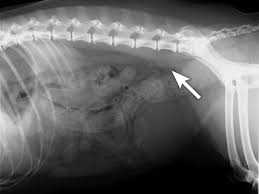

Signs Of Rectal Cancer In Dogs / Constipation In Dogs Vca Animal Hospital : Collapsing, weakness, and general lethargy (not greeting people at the door like usual or less interaction) are common signs of cancer, says jake.. We sometimes find things during rectal exams as well. Changes in body weight, appetite and vitality are potential signs of cancer of the colon in your pet. Other clinical signs include pain and fever. When the digestive process is interrupted due to gastrointestinal problems associated with colon cancer, a dog who seems to be healthy with no change in eating habits, could begin to experience vomiting and weight loss. This is due to the loss of nutrients and vitamins as food is not digested properly.

Unexplained lumps and bumps several forms of cancer can cause lumps or bumps on your dog's body, including a mammary gland tumor. They occur in any breed but are more common in spaniel breeds. But sometimes there are little or no signs, at least early on. Symptoms of colon cancer in dogs a dog with colon cancer will develop diarrhea and will vomit. Other signs of canine abdominal cancer include anemia, lethargy, diarrhea, bloody stool, dark colored stool, loss of appetite, and loss of sleep. The growths called rectal polyps occur infrequently in dogs. Scooting his hind end along the ground Diarrhea, constipation, and vomiting also show anything will go incorrect with your pet's digestive tract. Abnormal discharge from the eyes, mouth, ears or rectum. Signs include straining to defecate, blood in the feces, and diarrhea. We sometimes find things during rectal exams as well. Although in older dogs it can also be a symptom of arthritis. Collapsing, weakness, and general lethargy (not greeting people at the door like usual or less interaction) are common signs of cancer, says jake.

As a result, he will lose weight, have a decrease in appetite, and can quickly become dehydrated. Dogs suffering from rectal tumors usually have difficulty defecating. Signs and diagnosis the most common clinical signs of rectal tumors include straining to have bowel movements and blood in the stools. The polyps are usually benign and do not spread to other tissues. Ten years is the average age of affected dogs.

Ten years is the average age of affected dogs. Treatment protocol varied with six dogs undergoing surgery and. Mammary gland tumors in dogs The bleeding is usually minor. Affected dogs tend to suffer from diminished appetite, which results in weight loss and lethargy from lower blood sugar levels. The growths called rectal polyps occur infrequently in dogs. Changes in body weight, appetite and vitality are potential signs of cancer of the colon in your pet. But sometimes there are little or no signs, at least early on. Those are all classic signs. Abnormal discharge from the eyes, mouth, ears or rectum. When the digestive process is interrupted due to gastrointestinal problems associated with colon cancer, a dog who seems to be healthy with no change in eating habits, could begin to experience vomiting and weight loss. This is usually a severe lameness, where the dog cries in distress if you try to touch the sore place. When we palpate your dog, or when we feel your dog's abdomen as part of the exam, we'll often find a large spleen or a tumor.